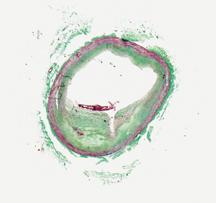

The first three images, courtesy of Professor Takashi Akasaka of Wakayama Medical University and Teruyoshi Kume, M.D., Kawasaki Medical University, shows OCT, IVUS and histological images of the same eccentric fibrous lesion with a calcium deposit.

IVUS’ grainy, black and white images are sometimes hard to interpret, which has given rise to new technical innovations. Ik-Kyung Jang, M.D., Ph.D., Massachusetts General Hospital, assistant professor of medicine at Harvard School of Medicine, said IVUS has a resolution of 65 microns and better resolution is needed to visualize certain structures, including identifying components that make up vulnerable plaque.

“The biggest advantage with OCT is the resolution, which is 10-15 microns,” Dr. Jang said. “If you put IVUS and OCT images next to each other the difference is night and day.”

Giulio Guagliumi, M.D., Cardiovascular Department Ospedali Riuniti di Bergamo, Italy, is the principal investigator for the Optical Coherence Tomography for Drug Eluting Stent Safety (ODESSA) study. At TCT 2008, he said OCT complements, but does not replace IVUS. He said the technology offers resolution 10-30 times higher than IVUS and is much better for near field imaging, making it more useful in visualizing smaller lesions. He also said OCT can visualize thrombus more clearly than IVUS. However, Dr. Guagliumi said the limitations of current OCT technology are shallow depth of light penetration (1-2 mm) where as IVUS can see further into surrounding tissue (about 10 mm).